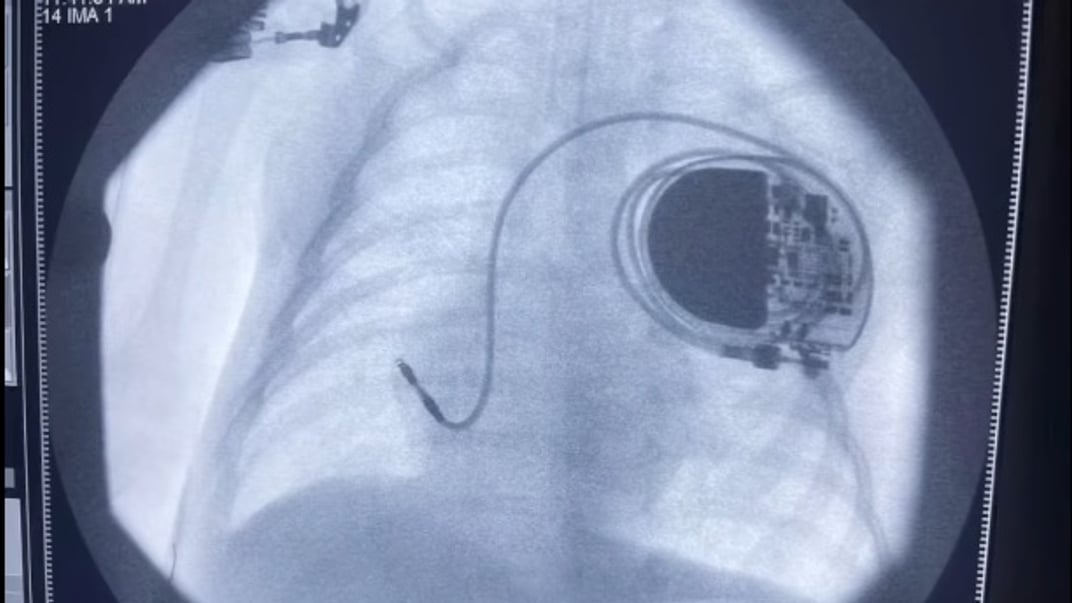

Медики в Одеській області провели унікальну операцію шестимісячному малюкові — імплантували електрод, який відновив природний ритм серця дитини.

Медики вирішили терміново імплантувати у провідну систему серця спеціальний електрод, який повністю відновлює природний ритм.

Малюк на час цієї операції важив лише 6 кілограмів. За даними одеських медиків, це найменший за вагою пацієнт у світі, якому провели таку складну процедуру.